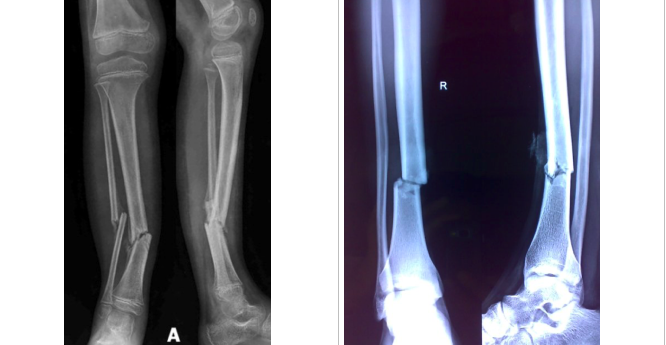

Describe this radiograph